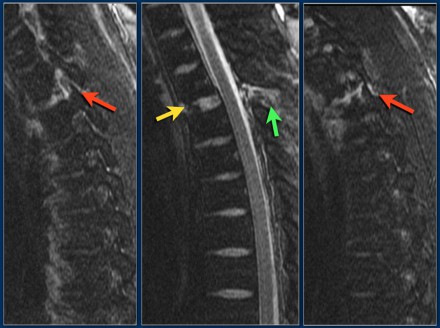

The findings are:

- The main feature is posterior distraction with horizontal fractures of posterior elements (red arrow)

- Avulsion of a spinous process (yellow arrow)

- Widening of facet joint (green arrow)

- Burst-type fracture

In this case some would call this a burst fracture with PLC-injury i.e. 2+3 points.

However the distraction is the most important finding, i.e. distraction and PLC injury, i.e. 4+3 points.